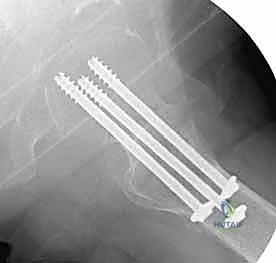

لماذا نستخدم 3 مسامير؟ (هندسة المثلث المقلوب)

يعتمد الأستاذ الدكتور محمد هطيف على مبادئ الميكانيكا الحيوية (Biomechanics) في التثبيت. يتم عادةً إدخال ثلاثة مسامير متوازية في عنق الفخذ. لا يتم وضعها بشكل عشوائي، بل تُرتب في شكل مثلث مقلوب (Inverted Triangle):

1. المسمار السفلي (Inferior Screw): يُوضع أولاً ليكون الدعامة الأساسية التي تستند على الكورتيكس السفلي الصلب لعنق الفخذ (Calcar)، وهو يتحمل أكبر قدر من وزن الجسم.

2. المسمار الأمامي العلوي (Antero-superior Screw).

3. المسمار الخلفي العلوي (Postero-superior Screw).

هذا التوزيع الثلاثي يوفر ثباتًا دورانيًا (Rotational Stability) ممتازًا ويمنع رأس الفخذ من الانزلاق أو الدوران حول محوره، كما يسمح بانضغاط الكسر (Compression) على طول خط الكسر، مما يحفز الخلايا العظمية على الالتئام السريع.

مميزات التثبيت عبر الجلد (Percutaneous Technique)

- تدخل جراحي طفيف (Minimally Invasive): لا يتم عمل شق جراحي كبير لفتح العضلات والأنسجة، بل يتم إدخال المسامير عبر شقوق جلدية صغيرة جدًا (حوالي 1-2 سم لكل مسمار).